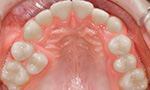

Die häufigsten Fehlstellungen

Nach Prüfung der Funktionen des Gebisses, wie zum Beispiel des Ineinanderpassens der Zahnreihen oder der Funktion des Kiefergelenks, steht fest, welche der folgenden Fehlstellungen vorliegt:

Überzählige Zähne

Es sind von Natur aus zu viele Zähne angelegt, die sich gegenseitig am Durchbruch hindern.